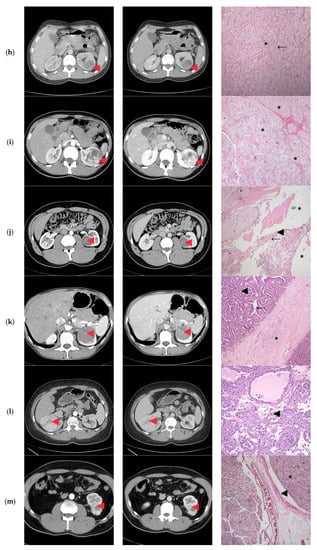

None of the patients had tumor invasion of the renal vein or the adjacent organs, calcifications, or macroscopic fat (Figure 2).

Figure 2.

Computer tomography findings in the cortico-medullary and nephrographic phases; Histopathological examination (a) Heterogeneous peripheral contrast enhancement, like the renal cortex (◄); Clear Cell RCC, Fuhrman grade 2. Tumor with compact and alveolar architecture (◄) of cells with clear cytoplasm, distinct cell boundaries and nuclei with nucleoli prominent at 100×. (b) Moderate nodular enhancement (◄); Clear Cell RCC, Fuhrman grade 1. Tumor with alveolar (←) and tubular architecture (◄) of cells with clear cytoplasm, distinct cell boundaries and nuclei with inconspicuous nucleoli at 100×. (c) Faint intra-tumoral contrast enhancement with mild progression in the nephrographic phase (◄); Papillary-RCC, type II. Tumor with papillary architecture (*) with pseudostratified layers (◄) of large cells with abundant eosinophilic cytoplasm, atypical nuclei with prominent nucleoli at 100×. (d) Heterogeneous contrast enhancement, less than the renal cortex in both phases, with an important necrotic component (◄); Adult cystic nephroma. A tumor composed of various sized cysts (◄) lined by flat cells separated by fibrous septa that contain smooth muscle (*) at 100×. (e) Intense contrast in the cortico-medullary phase, with an apparent central “scar” (◄) and less contrast enhancement compared to the renal cortex in the nephrographic phase; Clear Cell RCC, Fuhrman grade 1. Tumor with alveolar (*) and tubular (◄) architecture of cells with clear cytoplasm, distinct cell boundaries, and nuclei with inconspicuous nucleoli at 100×. (f) Bulky exophytic tumor with nodular peripheral contrast enhancement, like the renal cortex on the cortico-medullary phase and less than this on the nephrographic phase (◄); Clear Cell RCC, Fuhrman grade 2. Tumor with alveolar (*), tubular (◄) and cystic (o) architecture of cells with clear cytoplasm, distinct cell boundaries, and nuclei with nucleoli prominent at 100×. (g) Peripheral contrast enhancement like the renal cortex with an apparent “central scar” (◄) on the cortico-medullary phase and wash-out on the nephrographic phase, with the persistence of the “central scar”; Multicentric Chromophobe-RCC. Flocculent cytoplasm that condenses around the edges (“plant cell-like”, ◄) and pleomorphic nuclei (←) at 400×. (h) Faint peripheral enhancement on both phases (◄); Clear Cell RCC, Fuhrman grade 1. Tumor with the alveolar architecture of cells with clear cytoplasm (*), distinct cell boundaries (←), and nuclei with inconspicuous nucleoli at 100×. (i) Bulky tumor with peripheral enhancement (◄), like the renal cortex in the cortico-medullary phase, with progressive filling in the nephrographic phase; Clear Cell RCC, Fuhrman grade 2. Tumor with alveolar architecture (*) of cells with clear cytoplasm, distinct cell boundaries and nuclei with nucleoli prominent at 100×. (j) Faint spotted intra-tumoral enhancement on both phases (◄); Multiloculated cystic RCC, Fuhrman grade 1. Tumor with cystic architecture (*), with thin fibrous septae (◄) lined by clear cells (←). Tumor cells with inconspicuous nucleoli at 100×. (k) Faint, spotted intra-tumoral enhancement on both phases (◄); Metanephric adenofibroma. A tumor composed mainly of tightly packed tubules (◄) and secondarily long branching and angulated ducts (←). Tumor cells have scant cytoplasm and nuclei are small with no nucleoli, with no mitotic figures. Stroma is present as significant fibrous septa (*) at 100×. (l) Peripheral enhancement is like the renal cortex with the presence of a central non-enhancing area (“central scar”) (◄), on both phases; Oncocytoma. Small oncocytic cells (◄) with round, regular nuclei, no mitosis at 200×. (m) Peripheral enhancement like the renal cortex on the cortico-medullary phase and discretely less than the renal cortex on the nephrographic phase (◄); Clear Cell RCC, Fuhrman grade 1. Tumor with alveolar architecture (*) of cells with clear cytoplasm, distinct cell boundaries, and nuclei with inconspicuous nucleoli. The tumor invades a segmental renal vein (◄) at 100×. (n) Discrete nodular, peripheral enhancement (◄), less than the renal cortex on both phases; Papillary RCC, type I. Tumor composed of small cuboidal cells, with scant cytoplasm and round nuclei without nucleoli, arranged on a single layer on papillary cores (◄). Some of the papillary cores contain foamy macrophages (←) at 100×. (o) Peripheral enhancement less than the renal cortex on both phases (◄); Clear Cell RCC, Fuhrman grade 1. Tumor with a compact and alveolar architecture of cells with clear cytoplasm (←), distinct cell boundaries, and nuclei with inconspicuous nucleoli at 100×. (p) Bulky tumor with peripheral enhancement, less than the renal cortex on both phases (◄), with wash-out in the nephrographic phase; Clear Cell RCC, Fuhrman grade 1. Tumor with alveolar architecture (*) of cells with clear cytoplasm, distinct cell boundaries, and nuclei with inconspicuous nucleoli at 100×.